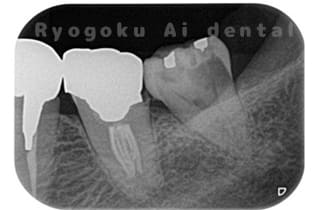

Case09

- 左上6番重度カリエス

- 治療内容

- クラウンレングスニング

-

- 治療費用

- 44,000円(根管治療、補綴は別途費用)

他院で抜歯と判断された歯です。クラウンレングスニングを行い、保存を試みました。現在も問題なく被せ物が入り、使用できてます。